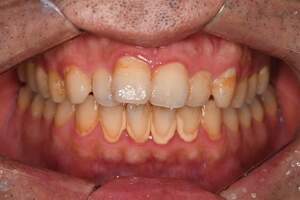

歯石除去

治療前

治療後

| 年齢 | 36歳・男性 |

| 主訴 | 歯石をとりたい |

| 治療内容 | 歯石除去 |

| 治療期間 | 30分 |

| 費用 | 約2,000円 |

| リスク・副作用 | ・歯ぐきの炎症が強いと歯石を取る際に出血することがあります。 ・処置後に歯がしみることがあります。 ・歯と歯の間に隙間ができるので、息が漏れ発音しにくいと感じることがあります。 ・歯ぐきの炎症が軽減すると歯ぐきが引き締まり、歯が長く見えることがあります。 |